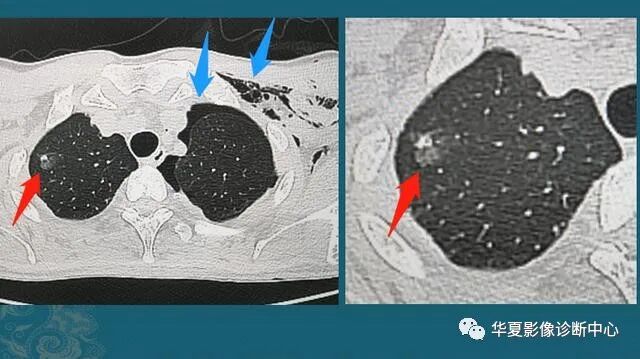

肺癌早期,表现为小结节